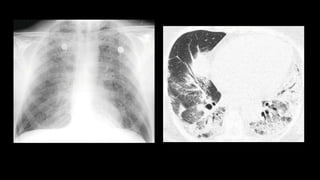

Radiography

• CXR: subtle

increase in

opacity at lung

base